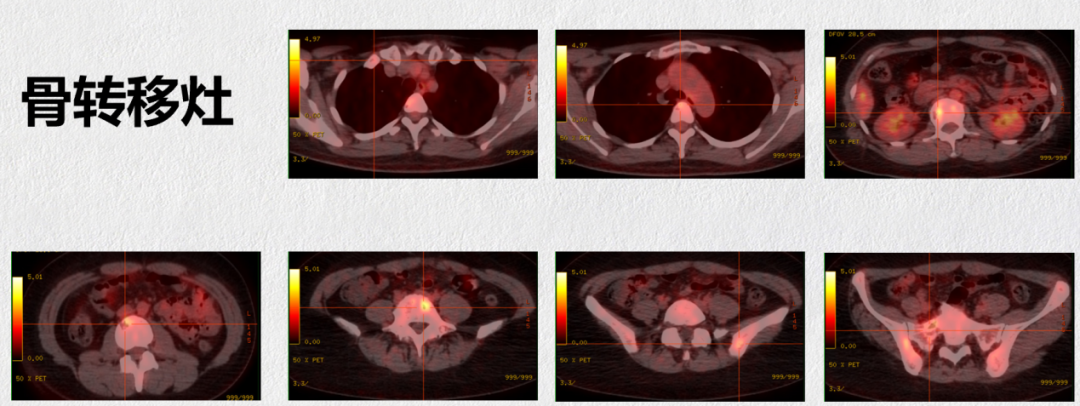

2018.10.31 PET-CT提示肝多发转移(S4,6,8段 SUVmax 3.7-4.2);骨多发转移:右侧第1前肋(SUVmax 1.6),椎体多发(SUVmax 2.6-4.5),双侧髂骨、脊柱(SUVmax 2.6-4.5)(RFS:76m)。

2018.10.31 PET-CT

这是一例绝经前乳腺癌患者,初诊为局部晚期,LuminalB 型。2012年行左乳癌改良根治术,术后予以辅助化疗、放疗及内分泌治疗。2018年复查PET-CT提示肝、骨多发转移,肝脏穿刺病理活检提示为HR+/HER2-,DFS为5年,属于继发性内分泌耐药患者。一线治疗予以哌柏西利+AI+OFS,肝转移灶疗效达PR(近CR),目前病情稳定,PFS超过32个月。